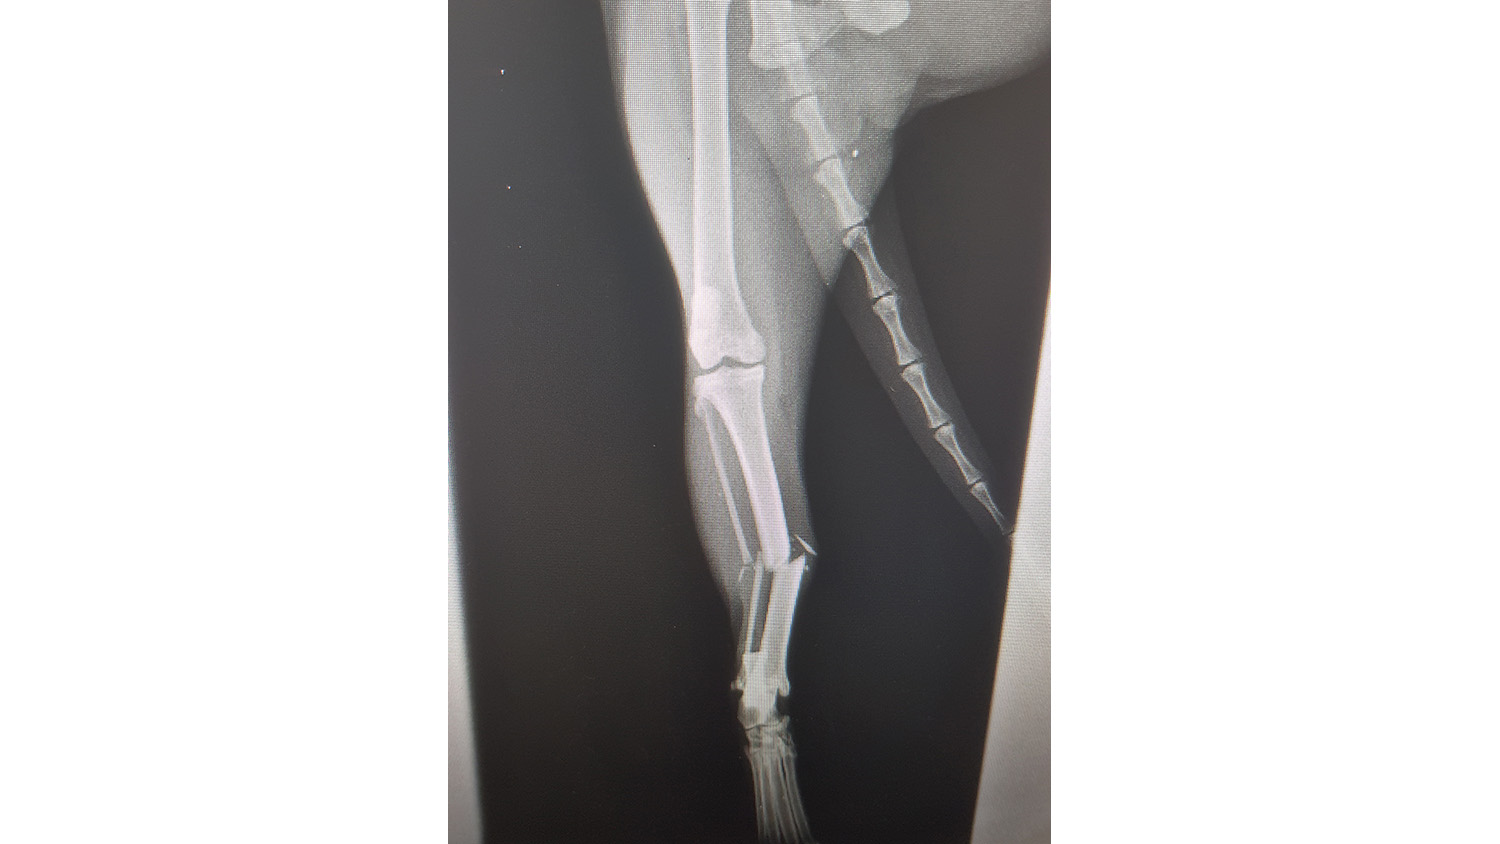

- radiographies osseuses : lors de boiterie, lors de douleurs dorsales, etc.

Fracture du tibia (chat)